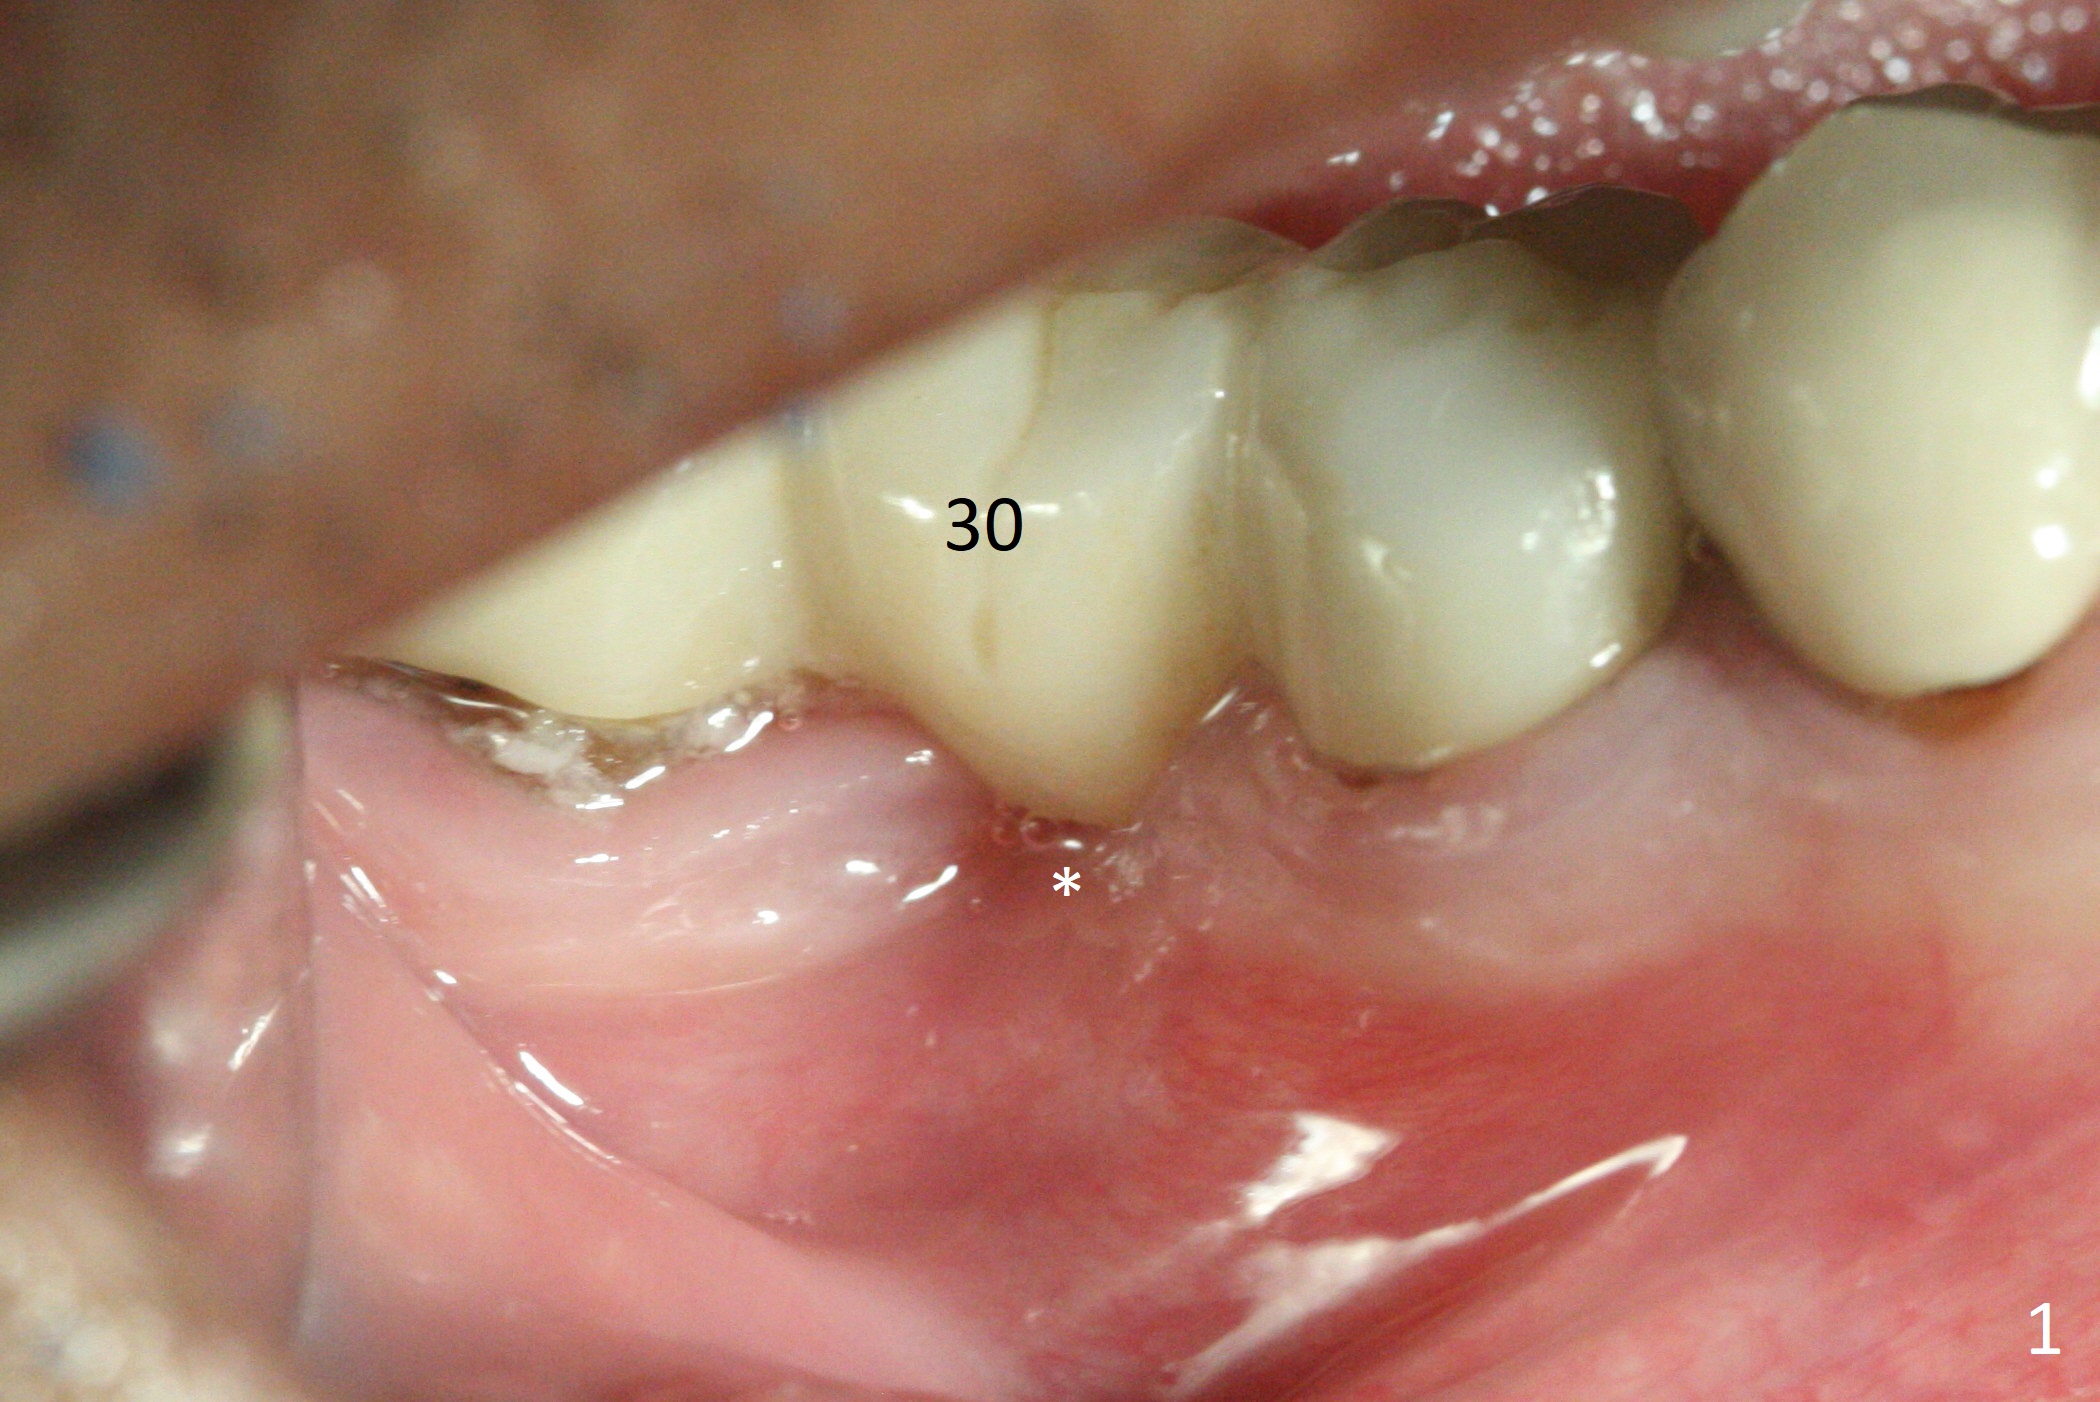

Preop examination shows that the buccal plate at #30 is atrophic (Fig.1 *). The mesiodistal width of the pontic is narrow as compared to the retainer at #31 (Fig.2). It appears that a narrow implant should be placed at #30 and should be able to sustain functional loading. After ridge reduction at #30 (Fig.3 ^) and extraction and debridement at #29, osteotomies at these sites are initiated with 1.2 mm and 2 mm drills, respectively. Probably due to low bone density, the osteotomy at #29 drops deep and close the Mental Loop (red dashed line). While the trajectory at #30 improves, the osteotomy at #29 remains close to the Mental Loop (Fig.4), asymptomatic with infiltration anesthesia. A 3x12(2) mm 1-piece implant is placed at #30 and 3.8x16 mm 2-piece implant at #29 (Fig.5,6 with insertion torque >50 and <50 Ncm, respectively). The large distal defect at #29 (Fig.3,5 *, most likely due to post-related perforation) is later filled with bone graft (data not shown). After placing an abutment at #29 and suturing, periodontal dressing is applied. Three months later, the meisal gap of #29 disappears while the distal one reduces (Fig.7 *). The abutment is changed to 4.5x4(4) mm one before reprep for impression. There is no bone loss 9 months post cementation (Fig.8) or 3 years 9 months post cementation (Fig.9). In fact the crown is lost at #31. At repeated request from the patient, a prefabricated post and crown will be fabricated for short term purpose while an implant is going to be placed at #19. The new crown at #31 has no occlusal contact (Fig.10), which may change over time.